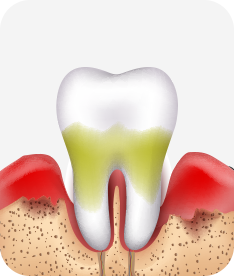

치주염 (중기~말기)

주기적으로 잇몸이 붓고 피가 나며, 욱씬하거나 우리한 통증이 나타남.

치주치료 및 정도에 따라 치주수술(잇몸수술)이 필요함. 향후 관리 정도에 따라 3~6개월 간격으로 내원하여 유지치료를 시행하여야 함.

치주염 (말기)

잇몸이 항상 부어 있으며, 이가

흔들리는 정도가 점점 심해짐.

치주치료가 필요하며, 정도에 따라 치아를 발치하여야 할 수 있음.